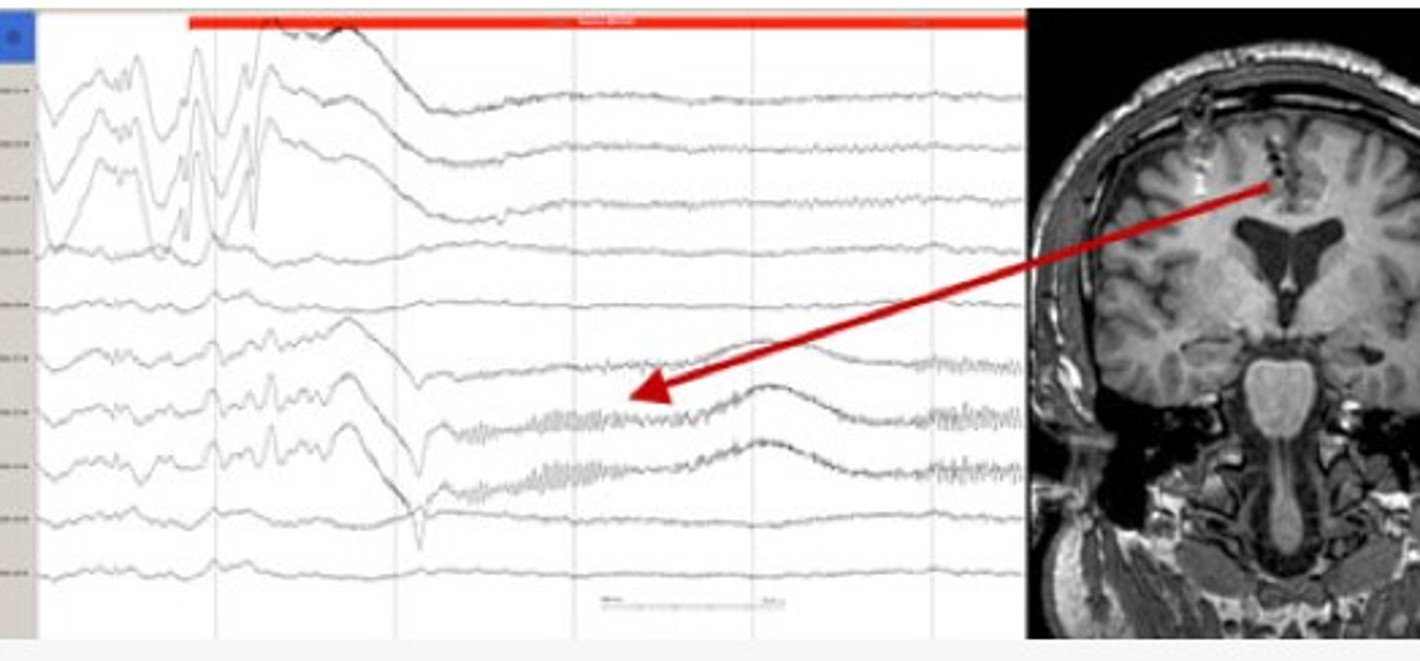

С помощью электродов аппарат может точно снимать фронтальные сигналы ЭЭГ, которые дают сведения об эмоциональных реакциях. Затем программное обеспечение обрабатывает сигналы и определяет эмоциональную реакцию, например, на музыку. Алгоритм не только анализирует эмоциональное состояние при воспроизведении музыки, но также фиксирует результаты в личном профиле пользователя. Затем

Для тех, кто не совсем в курсе, ЭЭГ или электроэнцефалограмма — это регистрация биоэлектрической активности головного для исследования его функционального состояния. Зачастую ЭЭГ применяют в диагностических (медицинских) и исследовательских целях. Регистрация электрической активности происходит неинвазивно, с помощью прикрепленных к голове электродов электроэнцефалографа. Сигналы от электродов усиливаются, после чего сигнал обрабатывается АЦП и записывается в цифровой форме.

На ЭЭГ определяется ритмичность электрической активности

Проведение экспериментов по психоакустике продемонстрировали стойкую взаимосвязь психических явлений с изменениями ЭЭГ. Прослушивание музыки и получение удовольствия от музыкальных произведений не стали исключением.